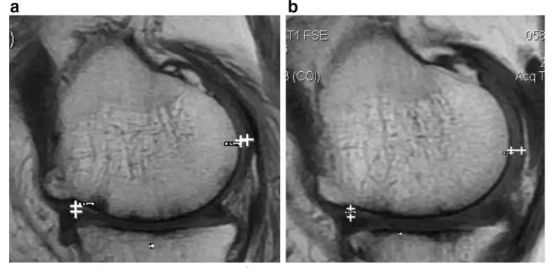

膝關(guān)節(jié)內(nèi)注射 ADSC(SVF)和 PRP 治療骨性關(guān)節(jié)炎

(J Transl Med, 2017)

參與者人數(shù):N=10

治療方案:將脂肪來(lái)源的基質(zhì)成分 ADSVF 和 PRP 注射到關(guān)節(jié)腔內(nèi),并在治療后 1 周、1 個(gè)月、6 個(gè)月、1 年、1.5 年和 2 年測(cè)試結(jié)果。

評(píng)估指標(biāo):WOMAC 評(píng)分丨MRI

研究結(jié)果:經(jīng)過(guò) 2 年的治療,WOMAC 評(píng)分也有所改善。6 分鐘內(nèi)的步行距離也顯著增加。60% 的患者軟骨體積增加。

注:如上圖所示,左圖為治療前,右圖為治療后,白色“+”處示意軟骨增厚。